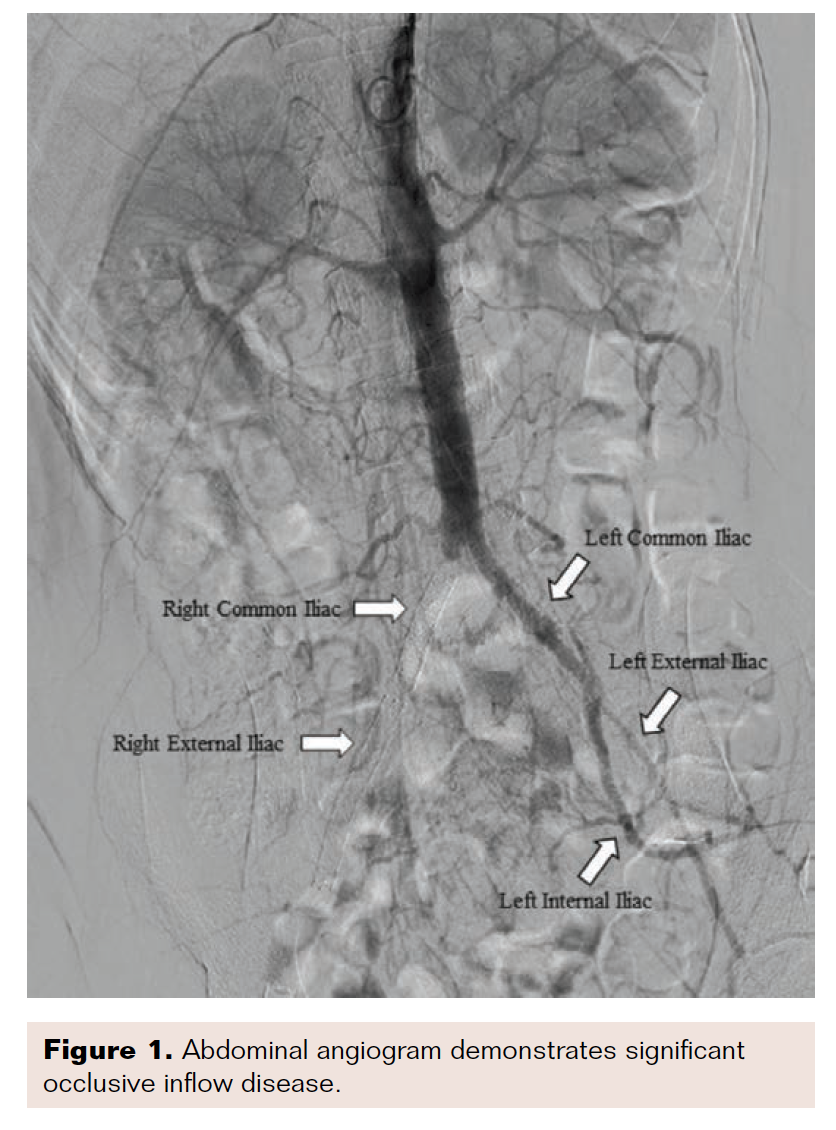

A 59-year-old woman presented with a history of bilateral above-knee-amputations, prior right-sided common iliac, external iliac, and common femoral arterial stenting, coronary artery disease with coronary arterial stenting, chronic obstructive pulmonary disease, hypertension, hyperlipidemia, diabetes mellitus (Type II), and tobacco dependence. The patient’s bilateral ischemic rest pain was not well controlled on oxycodone, gabapentin, and cilostazol. The ischemic rest pain, even with opioid therapy, prevented the patient from wearing her prostheses. Prior failed attempts to gain access to the bilateral occluded common femoral arteries left the patient with no obvious options for revascularization. After review of previous imaging, left brachial access was deemed most appropriate for a revascularization attempt. An OmniFlush catheter (AngioDynamics) was positioned at the level of the distal aorta for an abdominal aortography with runoff (Figures 1 and 2).

The angiogram demonstrated total occlusion of the right common iliac, external iliac, and common femoral stents. The right superficial artery had a flush ostial occlusion with no appreciable flow. Collateral flow filled in the right profunda femoris, which then provided collaterals to the stump. The left common iliac had appreciable flow, but flow became severely diminished at the start of the left external iliac artery. The left internal iliac fed the left profunda femoris through collateral flow. The left common femoral and left superficial femoral arteries were occluded, mirroring the right lower extremity.